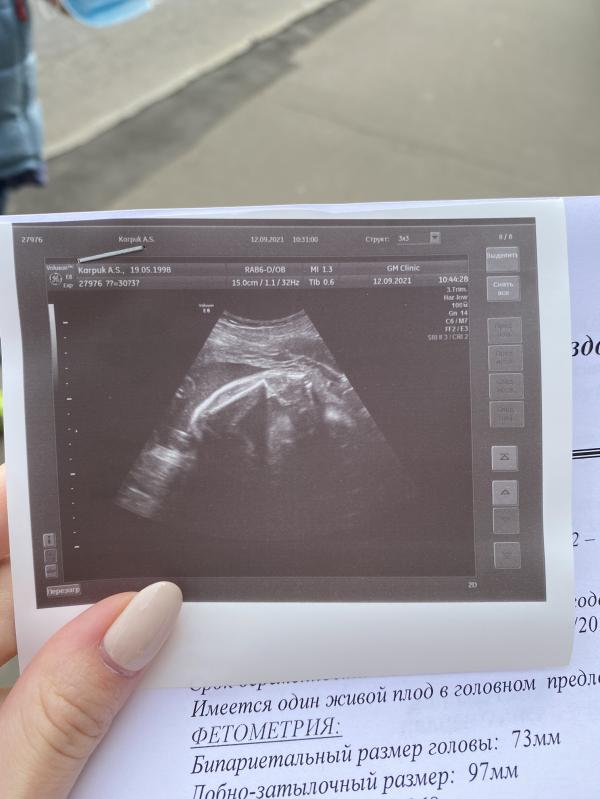

Скрининг на 31 неделе. Мелкая категорически отказывается показывать лицо, закрывается руками😂🤦🏻♀️

Поделитесь, пожалуйста, у кого какой вес плода был на 31-32 неделе? Наша 1280. Врач сказала, более-менее ок, но через месяц сделать ещё раз узи для уверенности